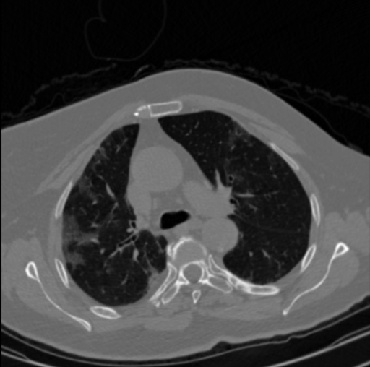

Early and reliable COVID-19 diagnosis based on chest 3-D CT scans can assist medical specialists in vital circumstances. Deep learning methodologies constitute a main approach for chest CT scan analysis and disease prediction. However, large annotated databases are necessary for developing deep learning models that are able to provide COVID-19 diagnosis across various medical environments in different countries. Due to privacy issues, publicly available COVID-19 CT datasets are highly difficult to obtain, which hinders the research and development of AI-enabled diagnosis methods of COVID-19 based on CT scans. In this paper we present the COV19-CT-DB database which is annotated for COVID-19, consisting of about 5,000 3-D CT scans, We have split the database in training, validation and test datasets. The former two datasets can be used for training and validation of machine learning models, while the latter will be used for evaluation of the developed models. We also present a deep learning approach, based on a CNN-RNN network and report its performance on the COVID19-CT-DB database.